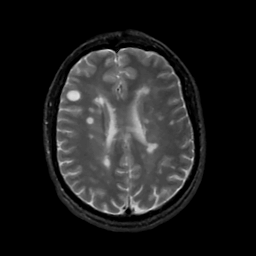

Tour 1: Next/Previous/Start: Look at the large round white spot in the right frontal region.

This is a relatively new lesion, and you can see how it

enlarges very rapidly over the next weeks. Look at the timeline cine.

With time, the lesion enlarges, there is a "halo" of white

(high) signal which surrounds the lesion. This probably represents the edema

which forms in reaction to the acute damage. At the end of the movie, you can

see that the lesion has nearly disappeared, with another lesions appearing.